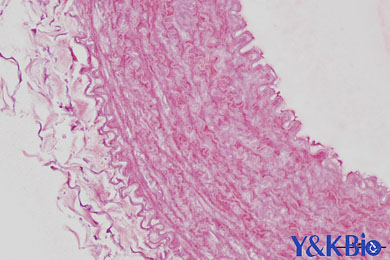

陕西依科生物技术服务有限公司致力于生物科研试剂的研发、销售及相关技术服务。从事的领域包括重庆VG染色,重庆EVG染色,重庆weigert弹力纤维染色,重庆维多利亚蓝染色和其他相关病理技术服务。同时,公司还建立了独立实验室,开展Real-time PCR和Western blot等分子生物学实验及其他相关检测。